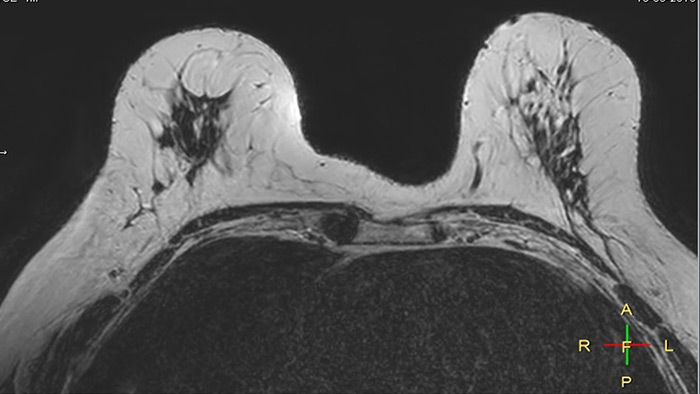

Compressed SENSE, scan time 3:54 min Voxels acq 0.8 x 0.72 x 1.8 mm Voxels recon 0.63 x 0.63 x 0.9 mm

C-SENSE factor 12

SENSE, scan time 6:32 min Voxels acq 0.8 x 0.8 x 1.8 mm Voxels recon 0.63 x 0.63 x 0.9 mm

SENSE factor 3

The time gain with Compressed SENSE was also used to increase resolution in order to help radiologists identify the tumor characteristics more confidently which may be used for a more personalized treatment. For example, in breast imaging, resolution is crucial for visualization of very small lesions. Compressed SENSE allows to scan thinner slices, allowing a 3D isotropic sequence which can provide increased diagnostic confidence for the radiologists.